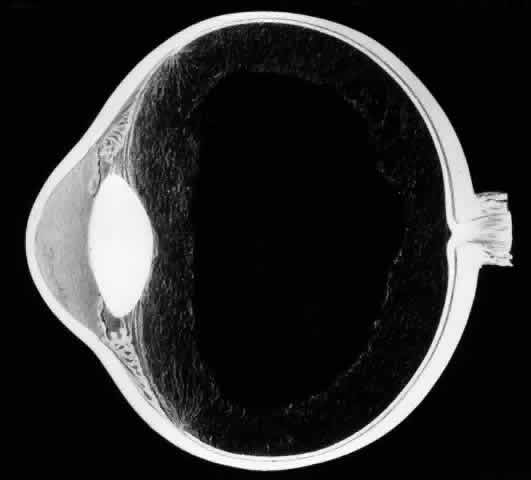

The earliest biomicroscopic changes preceding the development of a giant retinal tear were syneresis and liquefaction of the vitreous gel, converting the posterior and central portions of the vitreous body into a large lacuna (Fig. 14). Later, the anterior gel became condensed, and its posterior aspect formed an equatorially oriented membrane extending across the vitreous cavity (Fig. 15). This membrane did not oscillate with ocular movements, suggesting that it was under tension. Marked contraction of this membrane seems responsible for tearing the retina along the posterior border of the vitreous base (Fig. 16). Liquefied vitreous gel facilitated inversion of the posterior retinal flap (Fig. 17).

Fig. 14. The earliest biomicroscopic change in the vitreous prior to the development of a nontraumatic giant retinal break is liquefaction of the vitreous gel, which converts the central portion of the vitreous gel into a large lacuna.

Fig. 15. In later biomicroscopic changes preceding a nontraumatic giant retinal break, the anterior vitreous gel becomes condensed and a membrane forms its posterior aspect.

Fig. 16. Contraction of this equatorially oriented membrane extending across the vitreous cavity produces a giant tear along the posterior border of the vitreous base.